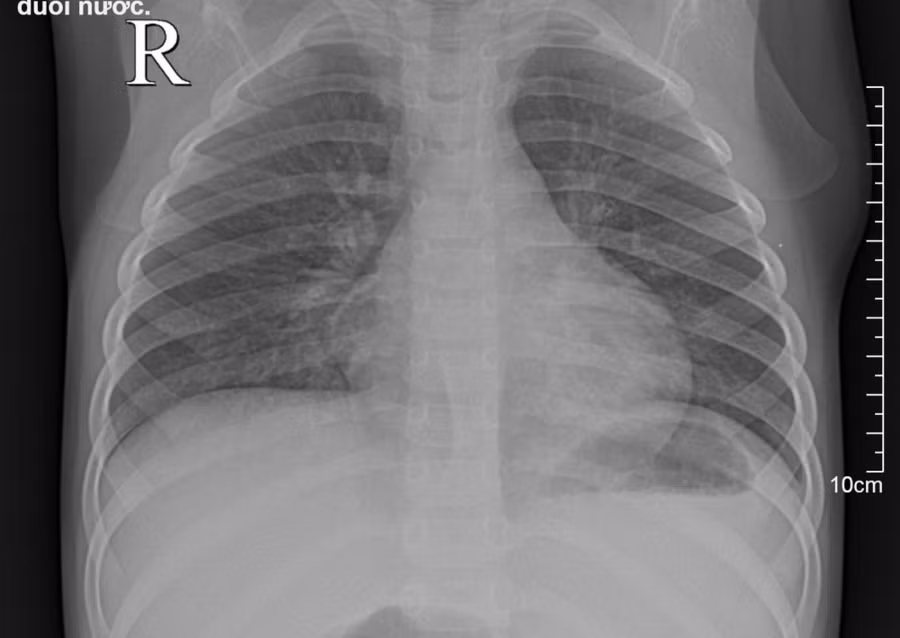

Bệnh nhi được thăm khám và chụp XQ phổi, kết quả XQ cho thấy hình ảnh phổi bé bị viêm. Các bác sĩ chẩn đoán bệnh nhi bị viêm phổi do đuối nước.

Hình ảnh X-quang phổi của bệnh nhi.